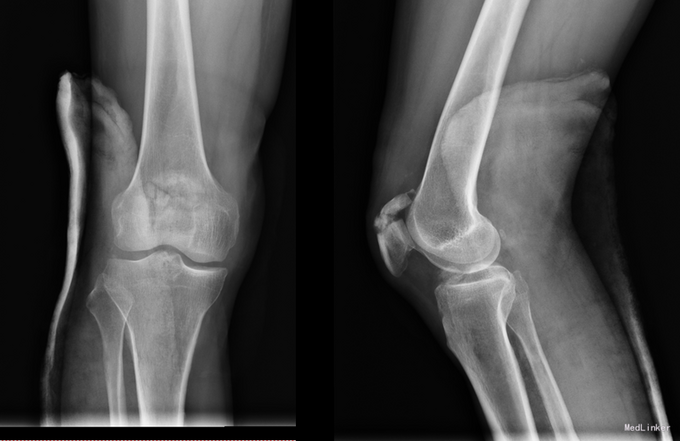

主诉:右膝关节疼痛活动受限9小时。现病史:9小时前骑摩托时发生车祸,患者当时头面部及右下肢受创,患者神志尚清楚,患者家属急送患者到当地黑山县医院,行头部CT及右下肢DR检查,头部CT提示:右颞部硬膜下血肿可能性大,右下肢DR提示右侧髌骨粉碎性骨折,给予对症处理后患者症状未见好转.为求进一步治疗,患者家属急送患者到我院急诊,行头部CT检查提示右颞部硬膜下血肿可能性大.为进一步治疗,将患者转入我科.

专科查体:患者神志清楚,定位准确,额纹对称,闭目有力,双侧瞳孔等大正圆,D=3.5mm,对光反射灵敏,双侧眼球各方向运动充分,无复视及眼震。双侧鼻唇沟对称,示齿口角不偏,伸舌居中。右下肢髌骨骨折,左下肢肌力4级,肌张力正常,双上肢肢肌力5级,肌张力正常,深浅感觉粗查未见异常。右侧巴氏征未引,左侧巴氏征(-)。